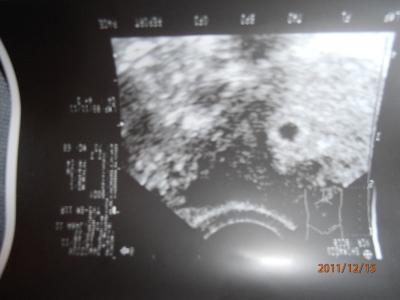

Hallo Mädels..... also als erstes.....bin heute 5+2......habe echt ziehen in UL.....und meine Brüste darf ich nicht anfassen...aua aua.....aber die sind schön voll und größer was nicht schlecht ist. War ja heute beim FA. und die Fruchtblase ist 7mm.....und oben sieht man ein miiiiiiiiiniiiiiiiii krümmelchen....... , oh die ganze strapatzen sind hinter mir....es sieht alles super aus, sagte mein Gyn. also werde ich mich entspannen ......hahahaha....übel...schwindel.... Ich danke von ganzen Herzen allem die an mich gedacht haben..... , Und ich denke an euch alle und drücke euch gaaaaaaaaaanz fest die daumen...... Habe mein nächste Termin am 5.1.12. und aber am 27.12. bekomme ich mein Mutterpass...... Hier ist mein Bildchen....... LG lillyh76

Bild zu US bild...... - Forum für August - Mamis